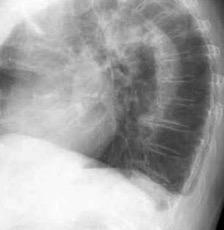

Paquipleuritis calcificada bilateral. En en lado derecho toracoplastia extensa con muñón residual pulmonar con bronquiectasias.